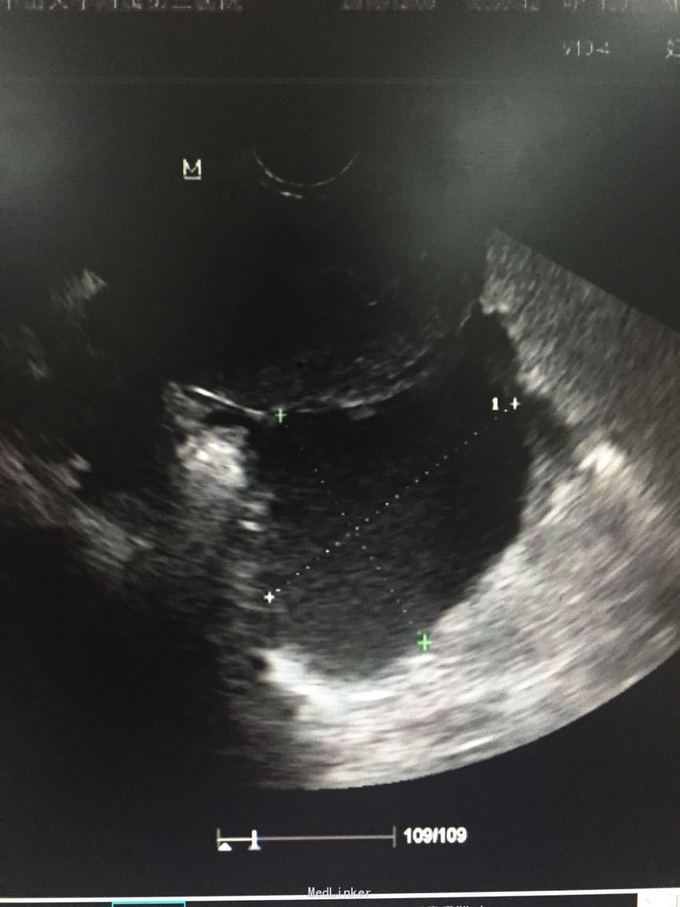

查体:右侧附件区可及一10*5cm包块,囊性,无压痛、反跳痛,左侧附件区可扪及5*5cm包块,囊性,轻压痛,无反跳痛。辅助检查:彩超:筛查附件区囊性包块,考虑内膜异位囊肿可能性大,左侧一个,大小58*49mm,右侧多个融合,范围91*48mm。

诊断:双侧卵巢巧克力囊肿。入院行剖腹探查术,术中见,大网膜、肠管、膀胱反折除及子宫前后壁可见附着褐色陈旧粘稠血块,大网膜与子宫底部及右侧前壁粘连,左侧卵巢增大约6*5*5cm,右侧卵巢增大约10*6*6cm,予以行腹式双侧卵巢囊肿剔除术+盆腔粘连松解术。术后病理:双侧卵巢巧克力囊肿。